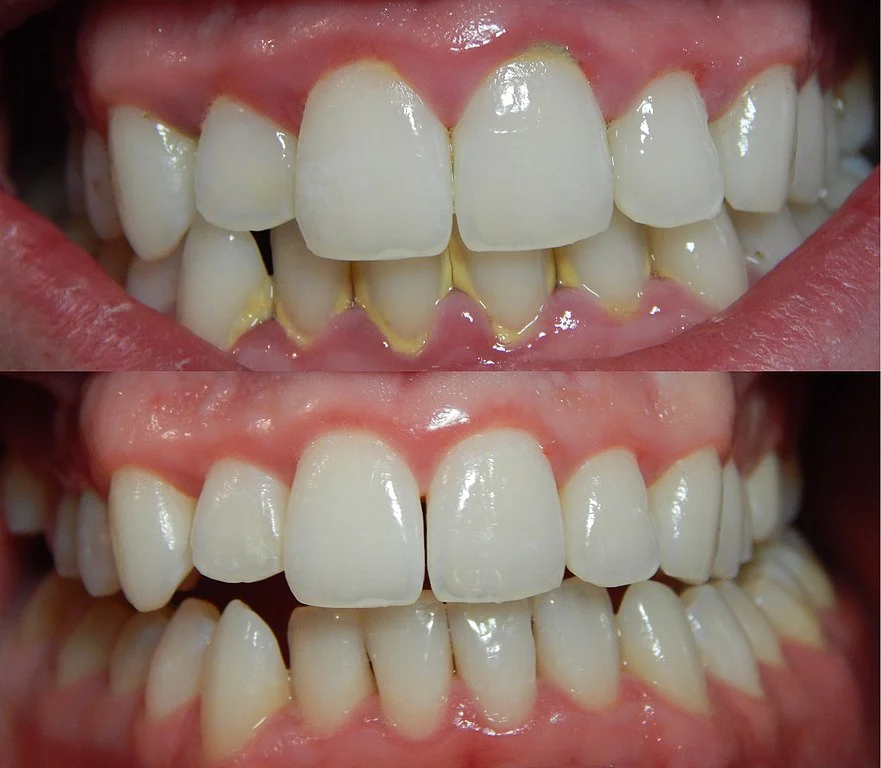

Stepping away from the causes, let’s talk about the tangible reality of gingivitis – what you actually see and sense when it sets in. This is where the abstract concept meets the physical manifestation in your mouth. Healthy gums are typically firm, pink, and hug the teeth snugly. They don’t bleed when you touch or brush them. Gingivitis changes that picture quite dramatically. The visual transformation is usually the first thing people notice, often catching a glimpse in the mirror while brushing. But the experience isn’t purely visual; there are tactile and even olfactory symptoms involved. Recognising these signs early is key to addressing the problem before it escalates.

The appearance can vary in severity depending on how long the inflammation has been present and other contributing factors. Initially, it might just be a subtle change, easily dismissed. But left unchecked, it becomes more pronounced, painting a clear picture of irritation and distress. The feel of your gums can also shift; they might become puffy or tender to the touch, a noticeable difference from their usual resilient texture. This combination of visual cues and physical sensations provides the crucial indicators that your gums need some serious attention.

What color are unhealthy gums affected by gingivitis?

This is one of the most telling visual signs. Healthy gums are typically a pale to medium pink colour, consistent throughout the mouth. When gingivitis takes hold, the colour shifts. The gums, especially along the edge right where they meet the teeth (the gum line), become noticeably redder. This redness can range from a bright, angry scarlet in early, acute inflammation to a deeper, more purplish-red hue in more chronic or severe cases. This change in colour is a direct result of the increased blood flow to the area as the body’s immune system responds to the bacterial toxins causing inflammation. So, if your gums are looking less like healthy pink flesh and more like an irritated, reddish border, gingivitis is highly likely.

What does stage 1 gingivitis look like?

In its earliest, most fundamental stage, often referred to simply as “initial gingivitis,” the visual signs might be quite subtle. You might see just a slight hint of redness or puffiness along the gum margin. The classic and often first noticeable *functional* symptom of stage 1 gingivitis, however, is **bleeding**. This bleeding typically occurs during mechanical action, like brushing or flossing. It might be just a tiny trace when you rinse, or more noticeable streaks in the sink. The gums might feel slightly tender or sensitive. At this stage, the inflammation is confined to the gingiva (the gums) and hasn’t yet started to affect the underlying bone or connective tissue. It’s reversible at this point, but its appearance is your body’s gentle nudge (or not so gentle, depending on the bleeding) that things are starting to go south.

Let’s get back to the heart of the good news: Gingivitis, as a stage of gum disease, is remarkably forgiving. Unlike its aggressive big sibling, periodontitis, the damage caused by gingivitis is confined to the soft tissues of the gums. It hasn’t yet attacked the bone and ligaments supporting your teeth. This crucial distinction means that yes, you absolutely *can* reverse it. Think of it as catching a cold before it turns into pneumonia. The symptoms are unpleasant, the body is fighting, but with the right care, you can make a full recovery, leaving no lasting damage. This potential for complete reversal is the most positive aspect of a gingivitis diagnosis and highlights why early detection and intervention are so vital. It offers a clear path back to health, provided you commit to the necessary steps.

Reversal means that the inflammation resolves completely. The redness disappears, the swelling goes down, the bleeding stops, and the gums return to their healthy, firm, pink state, tightly sealed around the teeth. The tissues regenerate to their original healthy form. There’s no lingering loss of support structure for the teeth. This favourable prognosis stands in stark contrast to periodontitis, where the damage to bone and connective tissue is permanent. While periodontitis can be managed to prevent further loss, the lost support cannot be naturally regained. Gingivitis, however, offers that reset button. It’s a powerful reminder that while gum disease can be serious, its initial phase is a wake-up call, not a final verdict.